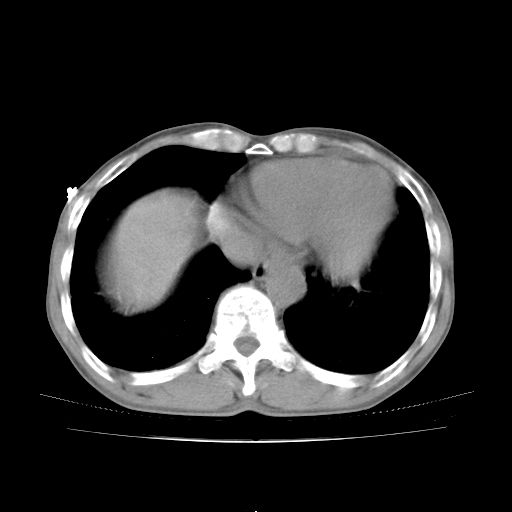

标题: CT25795:感冒后反复咳嗽两月余,痰中带血半月余。X诊断“肺 [打印本页]

标题: CT25795:感冒后反复咳嗽两月余,痰中带血半月余。X诊断“肺

1.双肺肺梗塞(理由:病灶呈三角形,与胸膜相连且局部胸膜肥厚,左心室增大)伴肺感染。

2.一元论双肺感染。

肺梗塞虽然有创意,但不现实。我考虑感染性病灶。

考虑两肺感染性病变,左肺上叶舌段肿瘤性病变待排;建议抗炎治疗后复查。